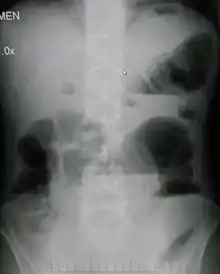

![]() يوضح التصوير بأشعة إكس على البطن وجود انسداد بالأمعاء الدقيقة والمريض في وضع الوقوف.لاحظ وجود مستويات متعددة من السوائل والغازات. يوضح التصوير بأشعة إكس على البطن وجود انسداد بالأمعاء الدقيقة والمريض في وضع الوقوف.لاحظ وجود مستويات متعددة من السوائل والغازات. | |

من ضمن الأشياء التي يكشف عنها التصوير الإشعاعي وجود انتفاخ بالأمعاء ووجود مستويات متعددة (أكثر من ستة مستويات) من السوائل والغازات في صور الأشعة التي تؤخذ على البطن والمريض في وضع الاستلقاء على الظهر تارة والوقوف تارة أخرى.